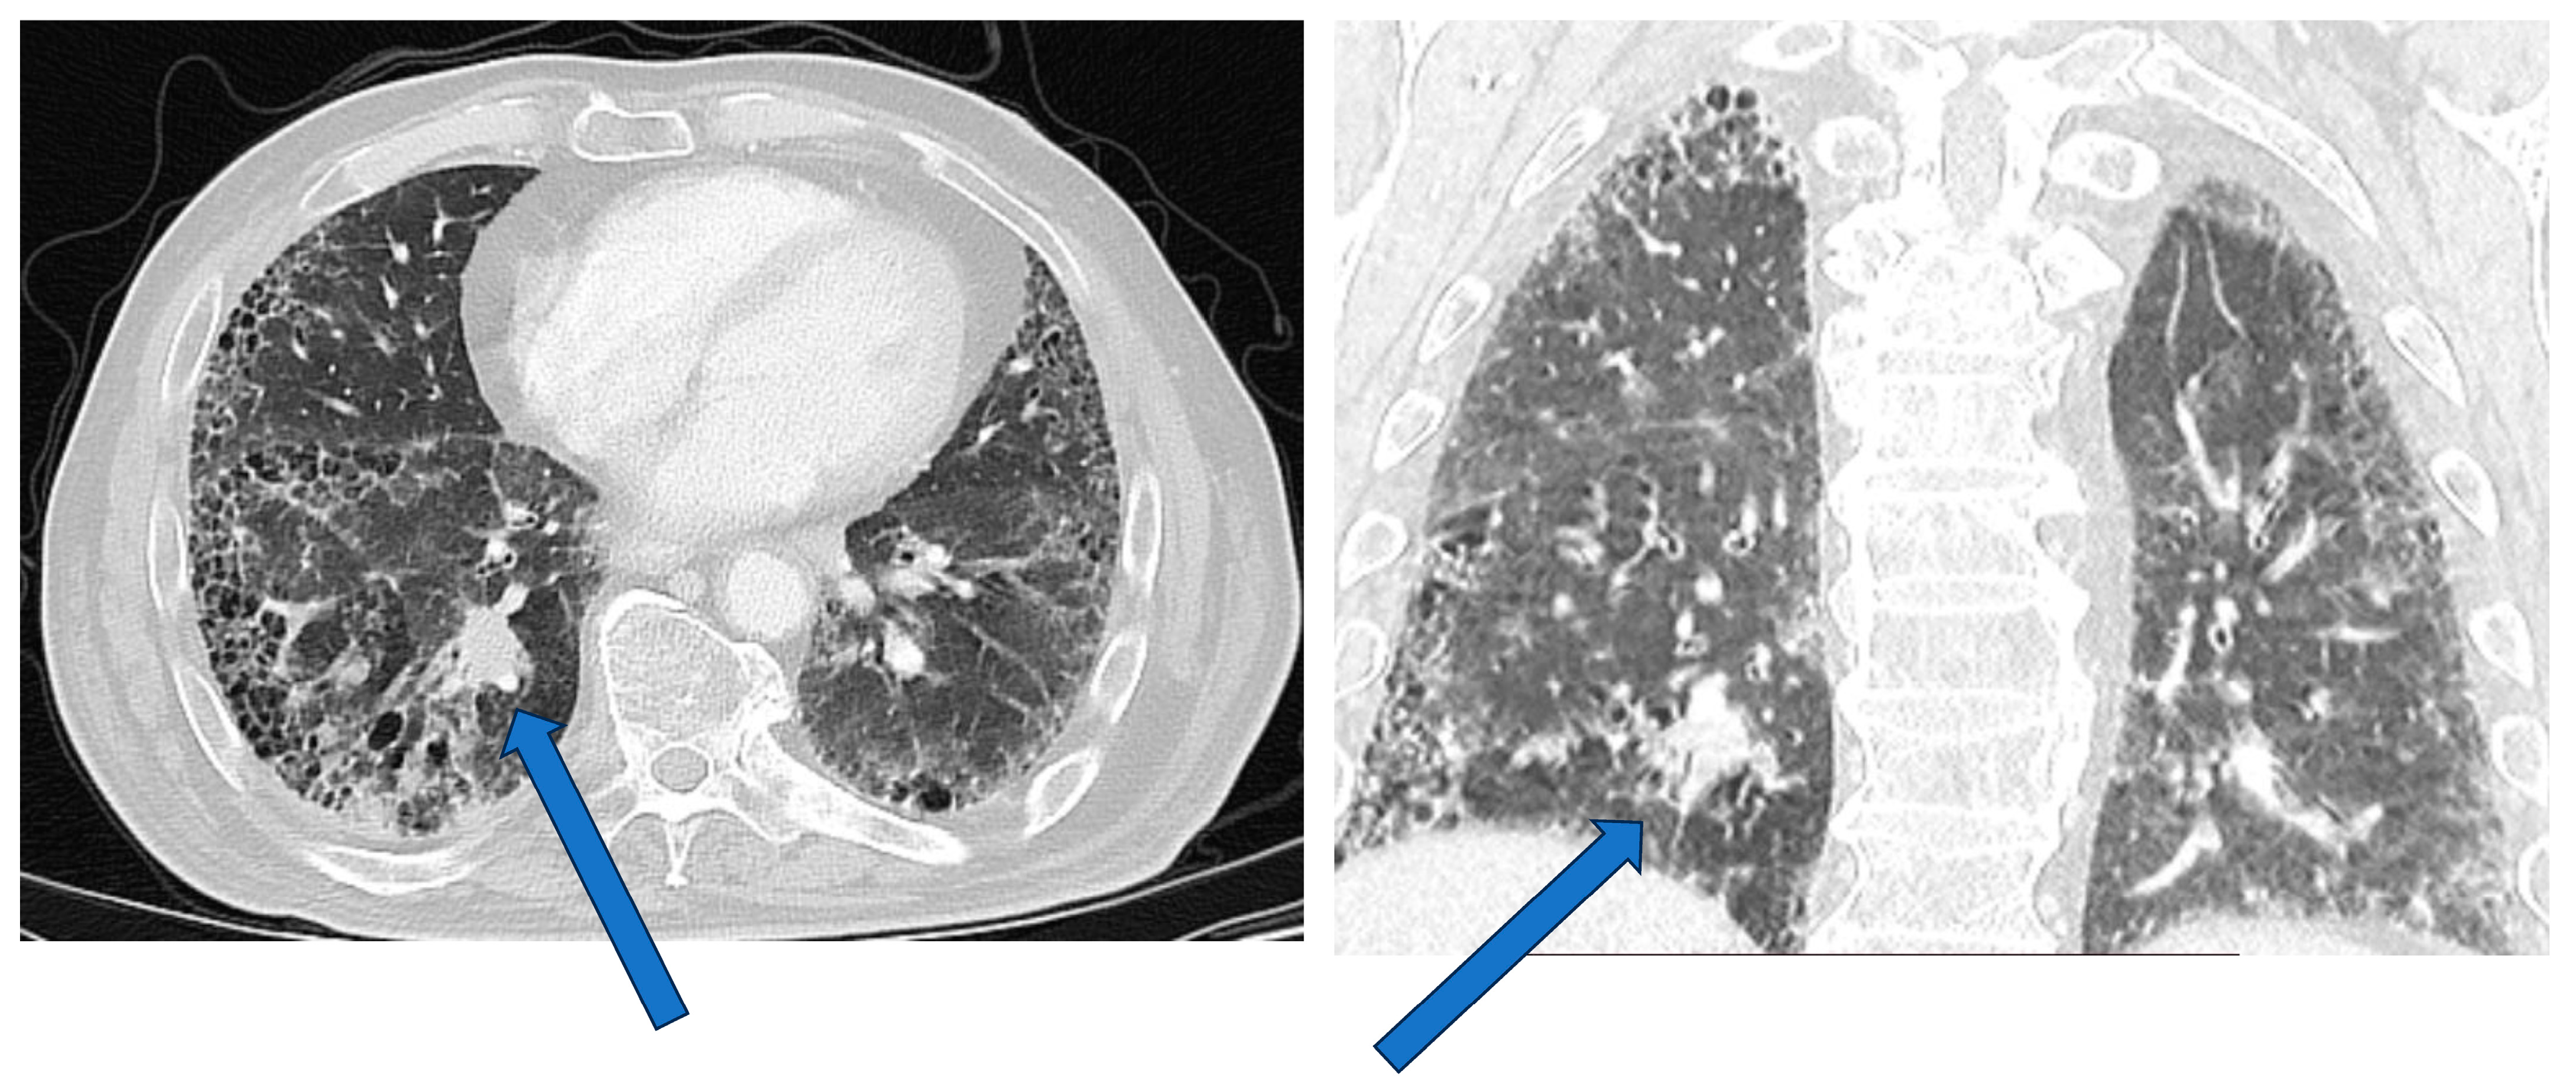

| HRCT | Tumors may be directly adjacent to fibrotic lesions, with an underestimation of tumor size. Reduced sensitivity and specificity in evaluating mediastinal lymph nodes (reactive mediastinal lymph node enlargement may be seen in ILDs without lung cancer) |